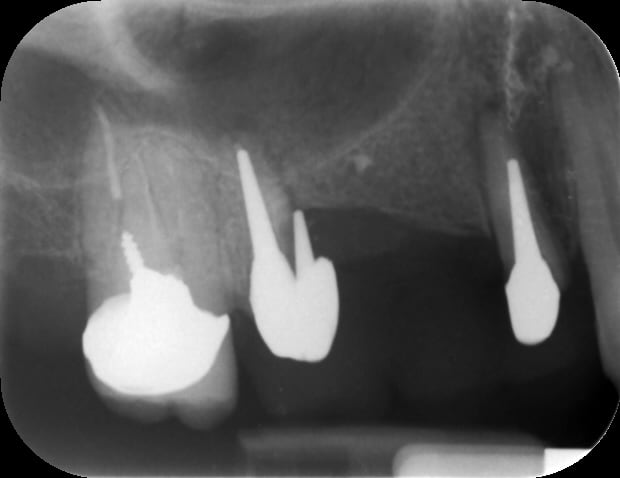

J'ai conclu par moi même qu'il fait de la merde en sur-équipant les patients , et récemment il fait de l'implanto . Voilà un superbe Not All on One , c'est un Ten On One . C'est beaaaaaauuu...)))

Img 3487 cuuqbi - Eugenol

Img 3488 h8ilol - Eugenol

Img 3489 cuhdog - Eugenol

Img 3491 pjrhic - Eugenol

Précision : Un correspondant et ami s'est chargé de l'extrimplantraction...car faut toujours avoir Dieu derrière soi pour combattre le diable devant les tribunaux . "Bin quoi ? Il était farpètement intégré mon implant , et dans le bon axe en plus !"